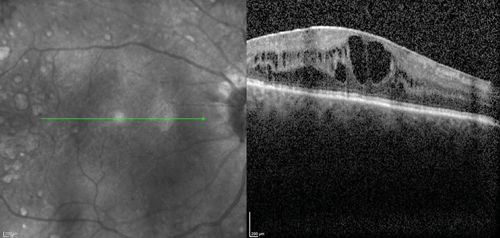

The clinical efficacy and safety of the drug have been also reported in two case reports of vitrectomised eyes with persistent DMO with both cases showing a desirable anatomical outcome. In one case, the authors have suggested that vitrectomy seemed to have enhanced the performance of the implant in-situ and achieved complete DMO resolution [19]. In a recently presented series of 20 post PPV eyes of 18 patients treated with Iluvien, a mean change of BCVA of +9 ETDRS letters (range -6 to +27) as well as mean reduction of CRT by -224µm (-595 to +126) were reported after a mean follow-up period of 201 days (range: 45 to 367 days) (SFO Paris 2016). Further real-life data of Iluvien in vitrectomised eyes with comparable clinical outcomes are awaited with interest. The author’s experience with the drug so far is in-keeping with published cases (Figure 1).

Figure 1: Case study for management of post-vitrectomy refractory DMO: (a) Pre-vitrectomy; (b) Post-vitrectomy; (c) Post six intravitreal anti-VEGF treatment with sub-optimal response; (d) Post-Iluvien one month. Complete resolution of DMO; (e) Post-Iluvien 10 months. Maintained response to treatment. (Courtesy of Mr David H W Steel - Sunderland Eye Infirmary).